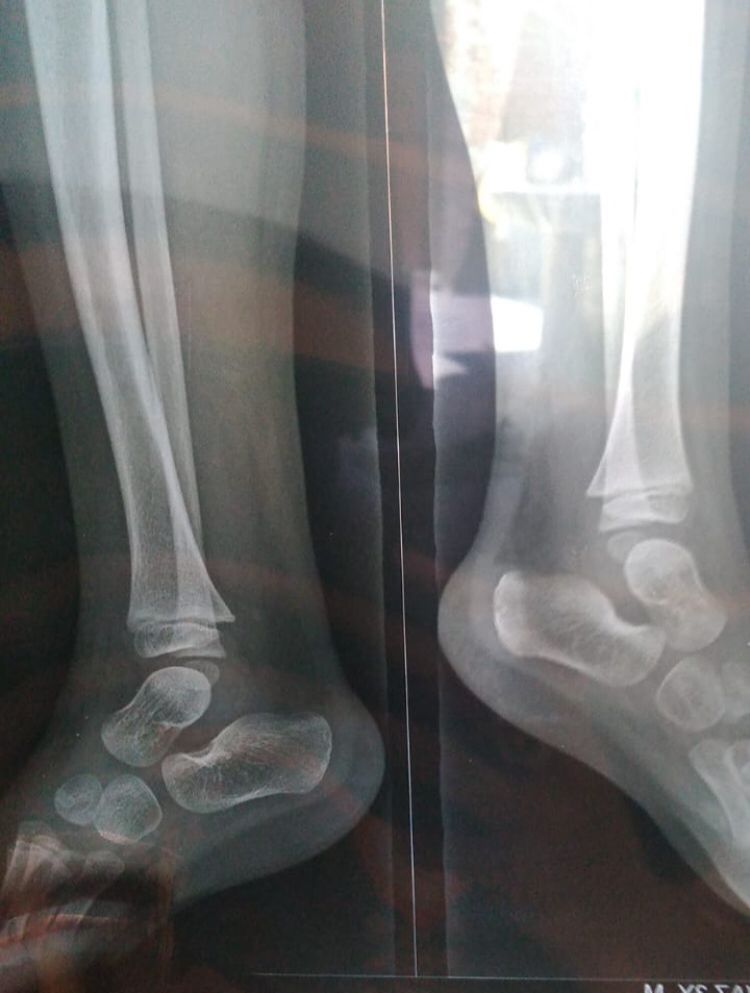

Please have look his x-ray

4 years ago

x-ray